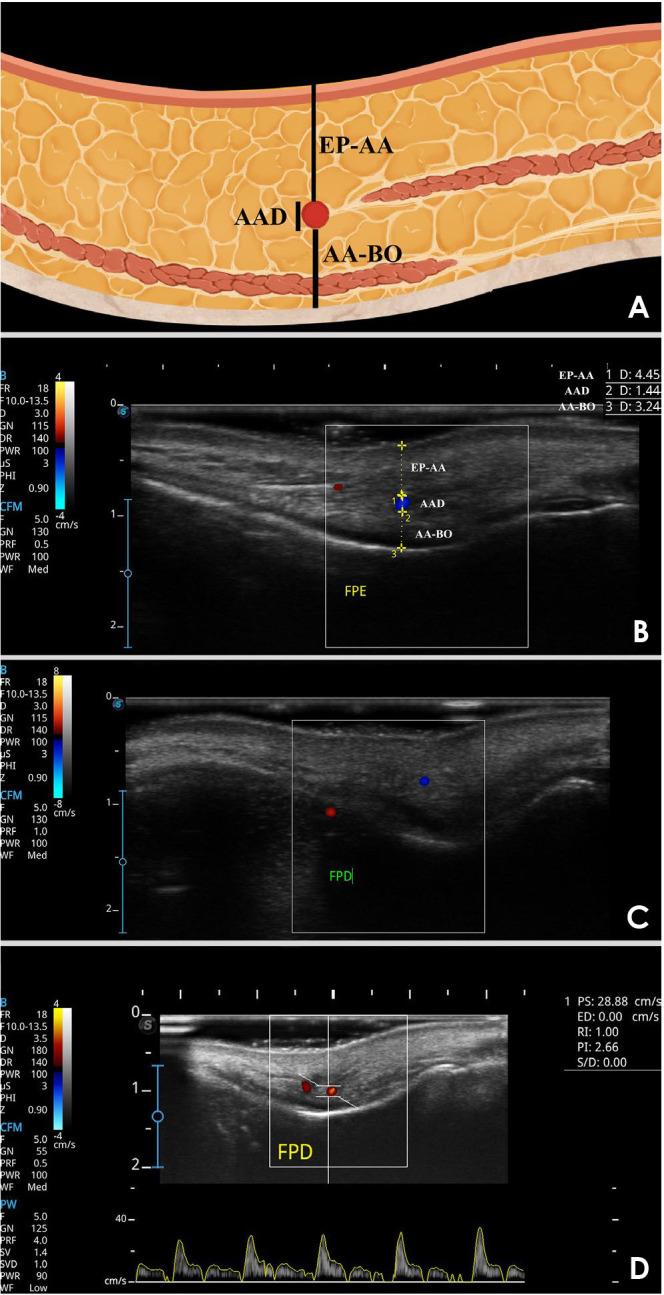

Purpose: Knowledge of the angular artery (AA) anatomy in the nasolabial fold is essential to prevent necrosis during esthetic procedures. This study aimed to assess the depth and hemodynamics of the AA in the pyriform space using 2-dimensional ultrasonography (USG), as well as color and spectral Doppler imaging.

Materials and methods: This study evaluated AA diameter, epidermis-AA distance (EP-AA), AA-bone distance (AA-BO), systolic velocity, diastolic velocity, pulsatility index, and resistance index. These parameters were analyzed in relation to independent variables, including age, sex, and body mass index (BMI). The study sample consisted of 58 Brazilian participants, with both hemifaces independently assessed by 2 trained examiners. Statistical analyses of the variables were performed with a significance level of 5%.

Results: The EP-AA distance was greater in men (5.8 mm) than in women (4.8 mm, P<0.05). BMI was also found to significantly influence the EP-AA distance (P<0.05). No independent variable affected the AA-BO distance. With respect to AA diameter, only age demonstrated a significant influence (P<0.05), with the diameter decreasing as age increased. Similarly, only age was associated with diastolic and systolic velocities (P<0.05), with each additional year corresponding to a reduction of 0.13 cm/s in diastolic velocity and 0.28 cm/s in systolic velocity.

Conclusion: USG demonstrated that AA depth in relation to the epidermis is greater in men and in individuals with higher BMI. Aging is associated with a reduction in both the diameter of the AA and its diastolic and systolic velocities.